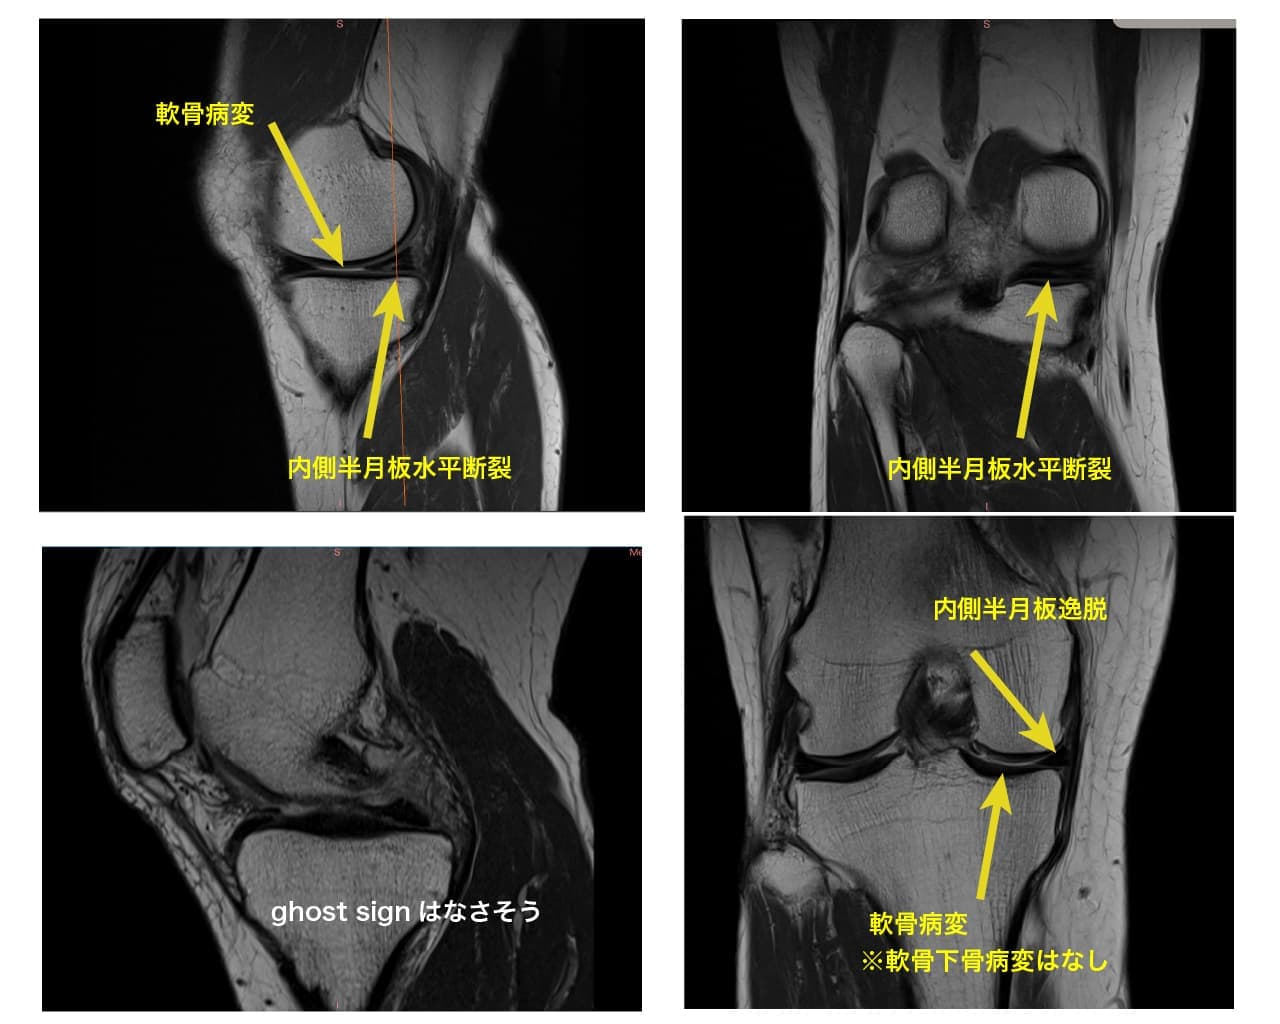

半月板には膝関節へ掛かる荷重ストレスを分散させるhoop機能というものがあります。

この機能が半月板損傷や逸脱によって破綻してしまうと、変形性膝関節症に発展していきます(急激な変形の進行の一因としてもhoop機能の破綻が関与していると言われています)。

その為、下のような画像が検査で判明したら、今のうちに出来る対応をしていく必要があります(MRIを提供してくれた患者様は、酷い変性は見当たらず経過観察となっていました)。

・荷重が偏らないように膝の使い方の再教育

・筋肉による膝関節の補強

・股関節や足関節といった関連部位の改善

など、様々な方法で状態を悪化させないようにしていきますが、『同じ症状』=『同じ問題』ではなく、リハビリの順序も一人一人違うため、その方にあった選択をしていく事が重要です。